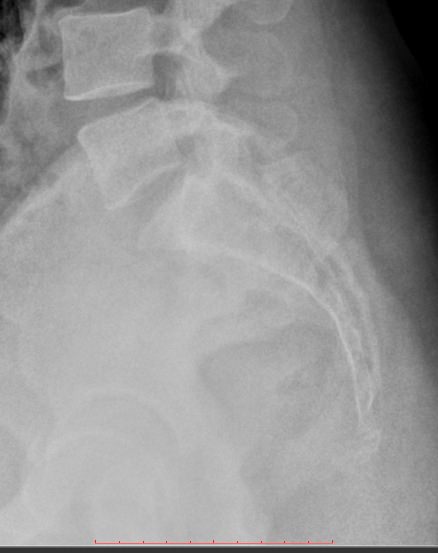

Рентгенографическое исследование при болях в нижней части спины хорошо визуализирует состояние костной ткани, дает возможность подтвердить диагноз и назначить наиболее эффективное лечение. Снимки выполняются в 2 проекциях: прямой и боковой. На рентгенограмму обычно попадают: 5-й поясничный позвонок, крестец и копчик. В прямой проекции также видны крестцово-подвздошные суставы.

Затем рентгенолаборант помогает принять положение для бокового снимка: лежа на боку, руки заведены за голову, ноги слегка согнуты. Длительность экспозиции ― те же 2 секунды, во время которых постарайтесь не шевелиться.